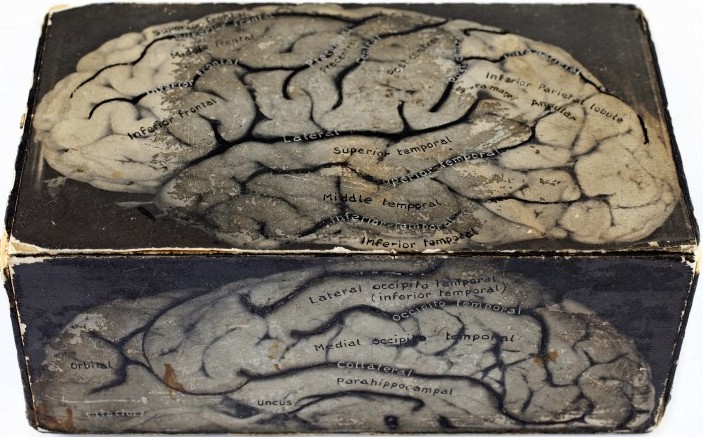

Cajal’s intricate drawings of the brain’s cellular structure show the hand of an impressive draughtsman – he made thousands of drawings on any scrap of paper he could find, accurately describing the brain’s complex circuitry (see picture above, drawing 1894; bottom: box model of the brain, mid 20th century, University of Aberdeen). In these beautiful, sinuous depictions, which suggest a beguiling “garden of neurology”, we find tree-like branches and roots and tissue strata, and marvel at such replications in nature.